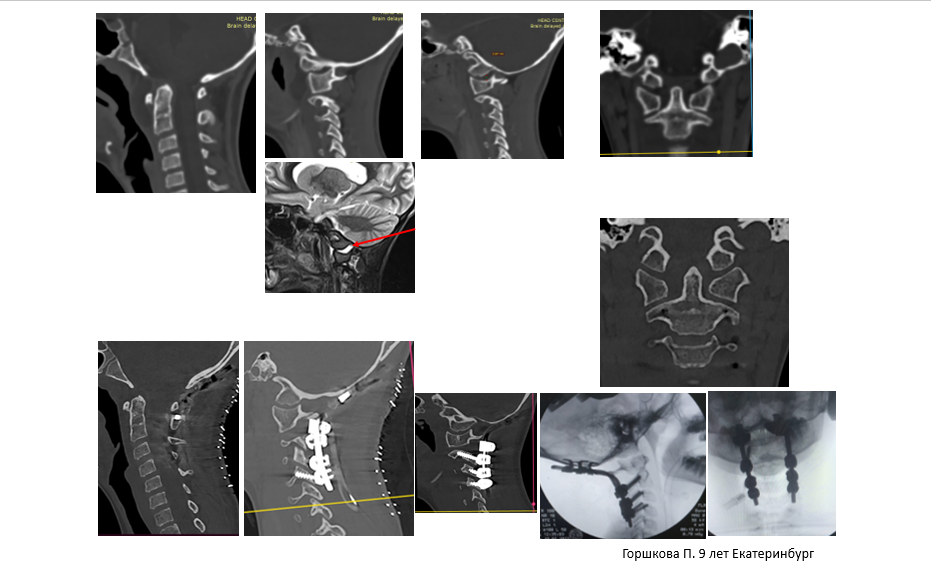

Как объясняет заведующий травматолого-ортопедическим отделением №1 Алексей Ластевский, у девочки очень редкая травма, описанная в медицинской литературе как атланто-окципитальная дислокация — травматическое разобщение затылочной кости и первого позвонка-атланта. Это условный «вывих головы». С 1965 года опубликовано всего 56 полноценных исследований, посвящённых этой травме, причём всего 3 публикации в мире — первого уровня доказательности. Описано всего 135 выживших пациентов с этим диагнозом в публикациях за период с 1965 года. Это значит, что раньше пациенты — в основном пострадавшие в ДТП — чаще всего погибали в связи с проблемами диагностики и интерпретации повреждений, применением неэффективных технологий лечения.

«Разрыв стабилизирующих связок между затылком и первым, вторым шейными позвонками очень опасен: пациент погибает либо сразу в момент травмы от повреждения жизненно важных центров — дыхательного и сосудо-двигательного, расположенных в продолговатом мозге, либо позже — от возникших осложнений. Невыполненная в ранние сроки операция, направленная на стабилизацию затылочно-шейного отдела, может привести к фатальному исходу. Основная проблема — это повреждение стабилизирующего комплекса на уровне краниовертебрального перехода», — комментирует спинальный хирург.

Операция, проходившая 19 июля в НИИТО, состояла из нескольких этапов. Сначала необходимо было вернуть взаимоотношения повреждённых сегментов в исходное состояние, а затем надёжно зафиксировать шейные позвонки и череп с помощью металлической конструкции и создать условия для формирования костного блока.